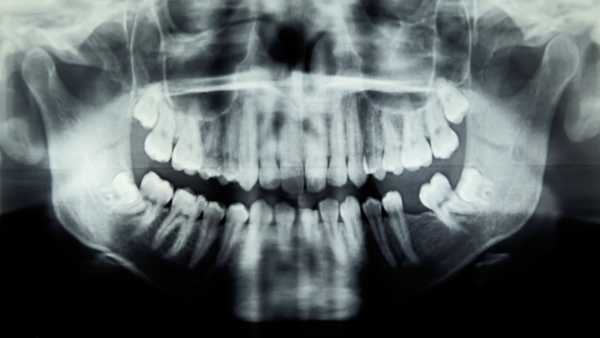

Під час незвичайної процедури чоловікові видалили зуб, а потім вставили його в око, щоб допомогти відновити зір. (Це зображення стокове і не пов'язане з випадком, описаним нижче.) (Зображення: yacobchuk/Getty Images)